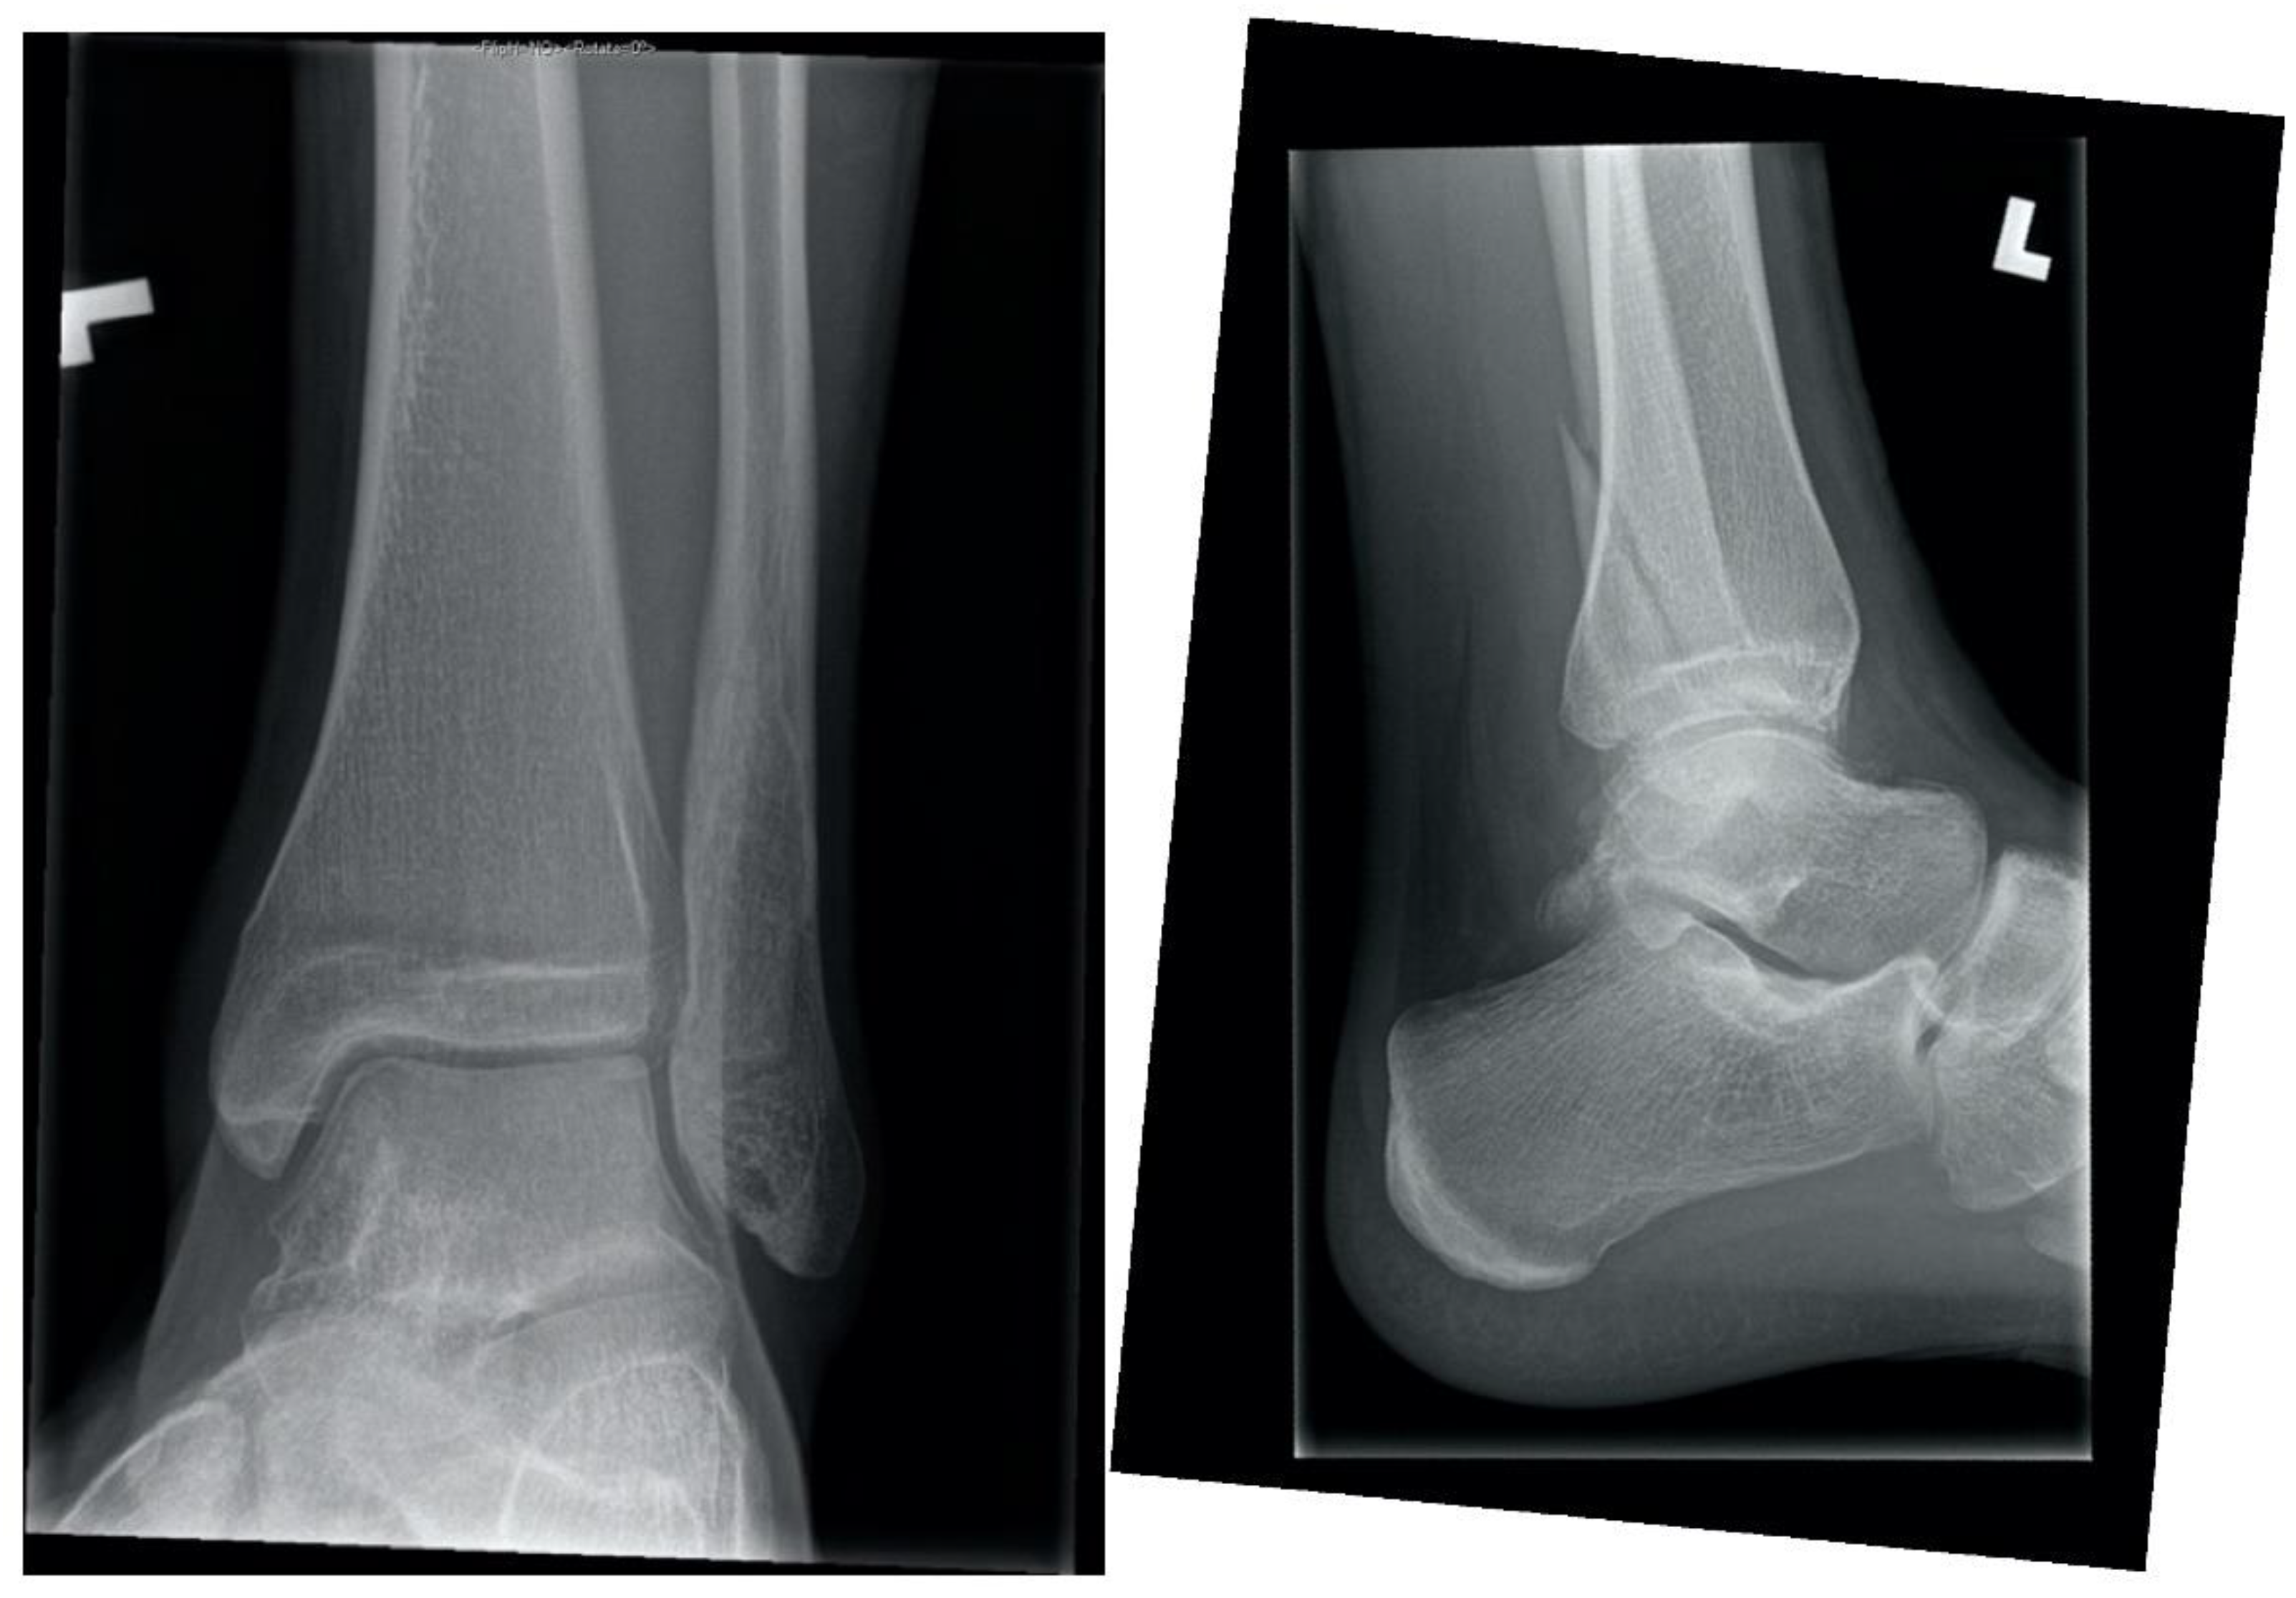

1.1. Ankle Fracture While Roughhousing, Eighteen Weeks in a 15-Year-Old Male

A fifteen-year-old male with no known medical history sustained a closed, minimally displaced, simple oblique trans-syndesmotic lateral malleolus fracture with no widening of the mortise. There was a remote history of occasional cigarette smoking and the patient was a current user of electronic cigarettes (EC). The fracture was reduced and splinted in a peripheral Emergency Room and referred to our centre for definitive management.

Initial treatment was circumferential casting and non-weight bearing. At one-week post-injury X-rays confirmed near-anatomic alignment. At four weeks post-injury radiographs were equivocal for callus, the patient’s exam was reassuring, and a removable cast-boot was placed with progressive weight bearing. At eight weeks post-injury, there was pain at the fracture site and inability to bear full weight. The patient was counselled to discontinue EC use. Cast-boot immobilization with weight bearing as tolerated was continued. There was no clinical or radiographic change at twelve weeks post-injury (Figure 1). Delayed union was diagnosed in the absence of healing beyond the expected four to six weeks required to heal this injury [1]. At eighteen weeks post-injury the fracture was no longer symptomatic, and radiographs confirmed bony union.

Figure 1.

Twelve-week ankle radiographs demonstrating no radiographic union after fibula fracture in a pediatric electronic cigarette user.